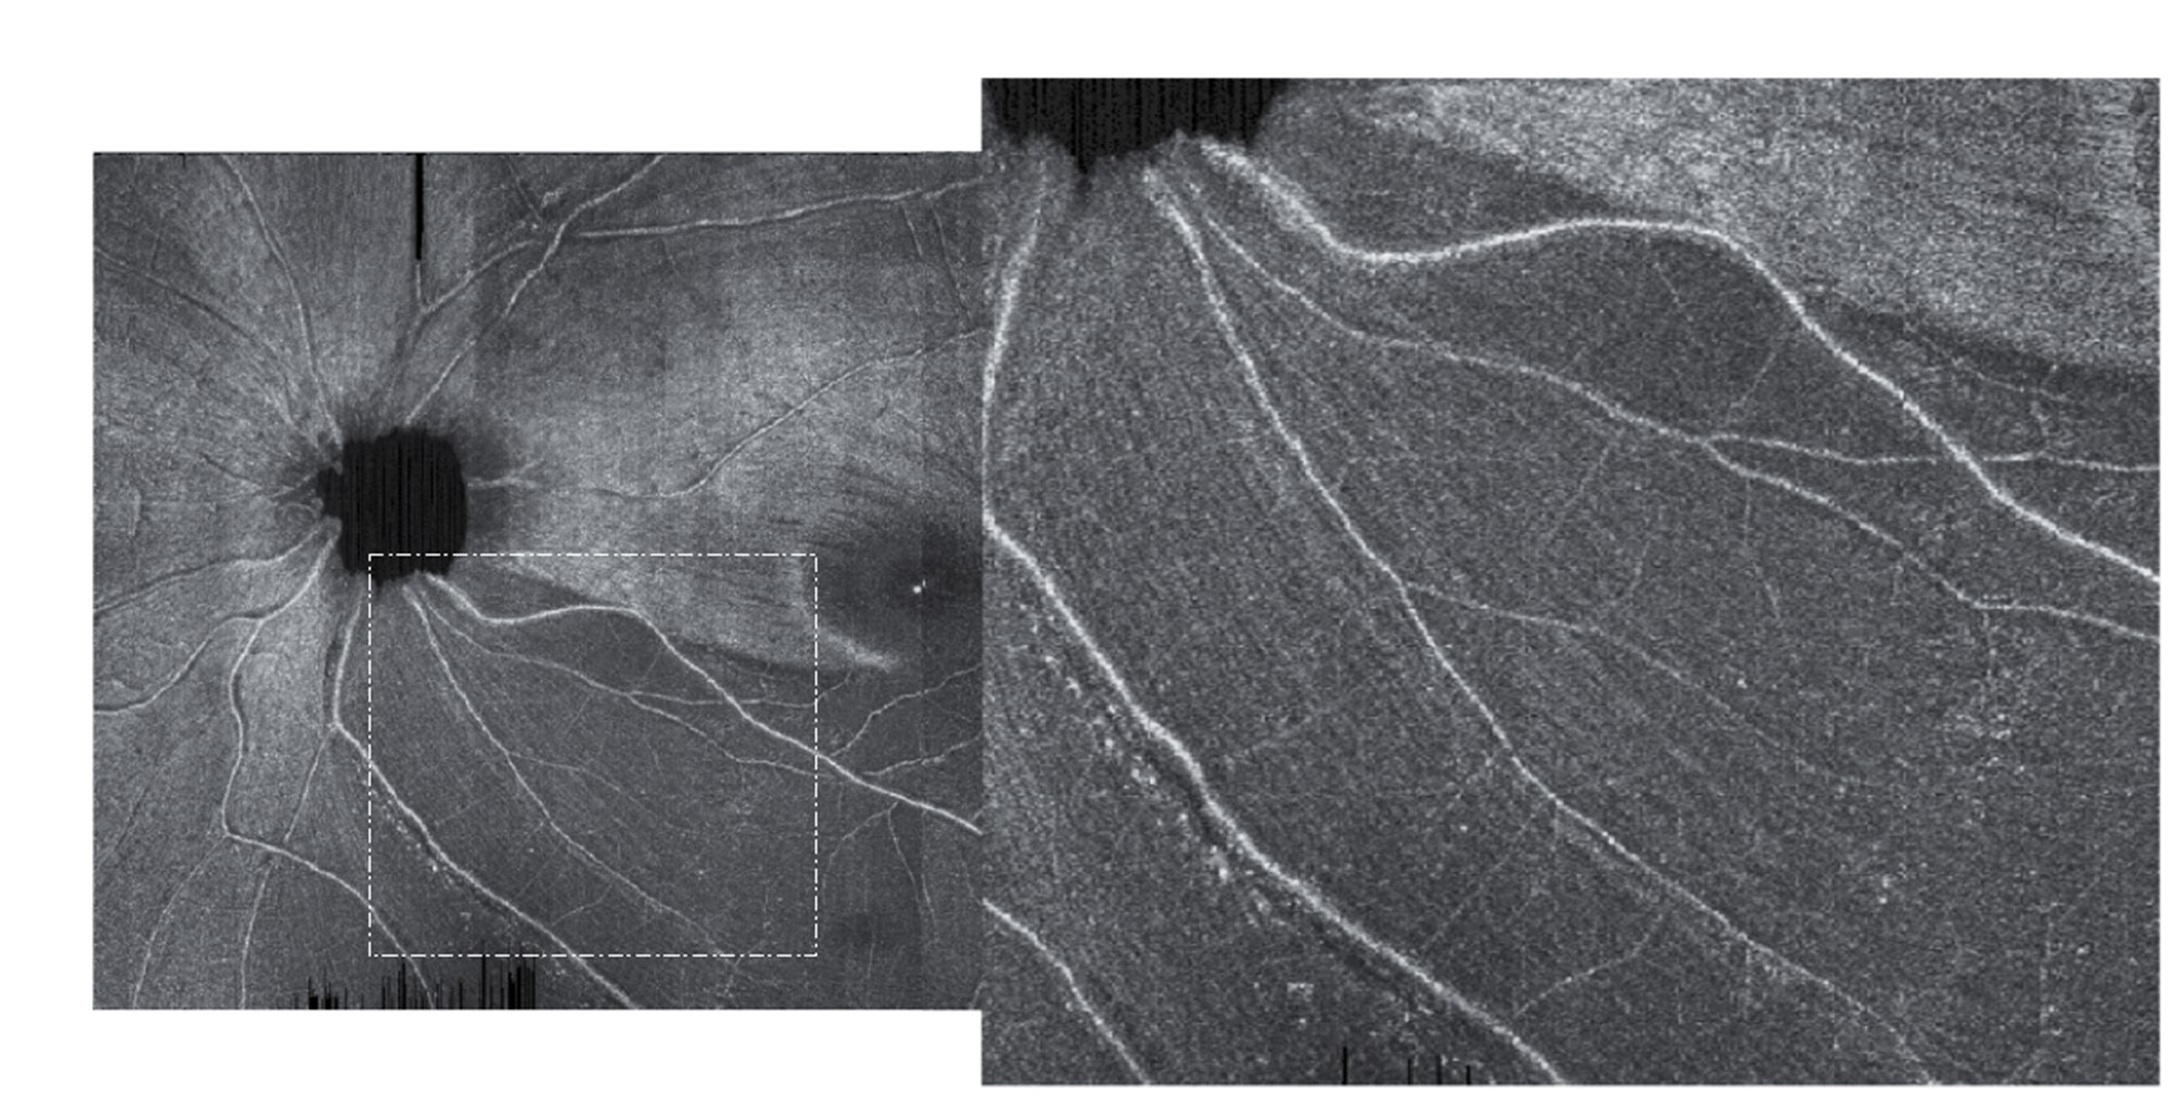

What motivated us to develop ROTA? Whereas OCT measurement of RNFL thickness has a relatively low test-retest variability, false negatives and false positives are common, which in part is attributed to the wide physiological variations in the distribution of the retinal axonal fiber bundles. The sensitivities of best-performing OCT parameters for detection of RNFL thickness abnormalities have been shown to be 65%-75% at specificities of 90%-95%.4 In eyes with high myopia, the specificity of OCT RNFL thickness analysis has been about 30%.5 The fact that individual axonal fiber bundles are not discernible from conventional RNFL thickness analysis has compromised the diagnostic performance of OCT to detect glaucoma. We have been studying the application of OCT for RNFL analysis for more than 10 years. The staggering challenges in discerning RNFL defects in early glaucoma motivated our team to engineer ROTA, or RNFL Optical Texture Analysis (ROTA). The methodology of ROTA and the clinical validation study were published in the March issue of Nature Biomedical Engineering.6 Just as the retinal capillary network embedded in the OCT scans can be visualized via OCT angiography analysis, the trajectorial details of individual axonal fiber bundles can be unveiled via extracting the axonal fiber bundles optical texture signature from standard OCT scans. The axonal fiber bundles exhibit a higher reflectance relative to the surrounding blood vessels and connective tissues because of the increased scattering of the axonal cytoskeleton. Applying a series of non-linear transformation of the normalized axonal fiber bundle reflectance signal, the trajectories of individual axonal fiber bundles can be uncovered, which enables intuitive visualization of RNFL defects that would otherwise be missed by conventional OCT analysis and red-free photography.

ROTA extracts the optical texture of axonal fiber bundles

Future development  ROTA can be applied in all commercially available OCT models; we are working with a number of OCT industries to deploy ROTA in clinical care. With high-resolution, high-speed OCT scans, it is feasible to visualize the fine details of the axonal fiber bundles within and beyond the macula, as well as over the peripheral retina. We believe ROTA can reset the paradigm of glaucoma diagnostics, enabling specialists and non-specialists alike to diagnose and monitor glaucoma and non-glaucomatous optic neuropathies with high precision.

High resolution ROTA